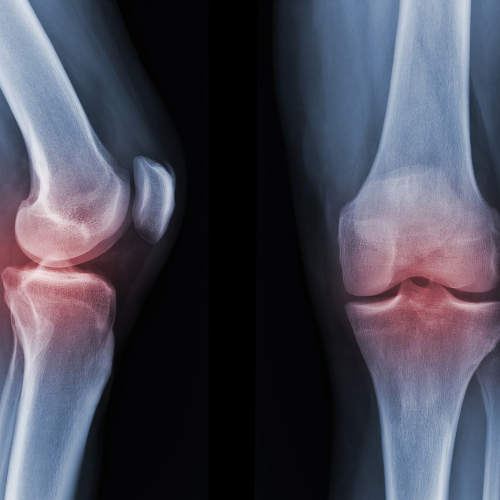

The Rheumatology Department at Surya Kiran Hospital specializes in the diagnosis and treatment of autoimmune and inflammatory disorders affecting the joints, muscles, bones, and connective tissues. Our expert rheumatologists provide comprehensive care to help patients manage pain, reduce inflammation, and improve mobility, with the goal of enhancing long-term quality of life.

- Diagnosis and management of rheumatoid arthritis, psoriatic arthritis, and osteoarthritis

- Osteoporosis screening and treatment

- Joint injections for pain and inflammation relief

The Rheumatology Department at Surya Kiran Hospital is equipped with advanced diagnostic tools and modern treatment facilities to accurately identify and effectively manage autoimmune and musculoskeletal disorders. Our infrastructure supports early detection, precise monitoring, and targeted therapy for a wide range of rheumatic conditions.